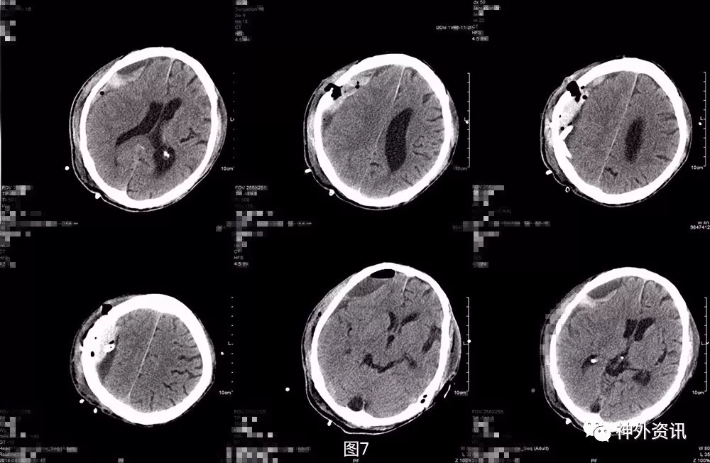

科室术前讨论,考虑患者两次手术后再出血,局部占位较大伴中线偏移,有对侧肢体肌力下降。有再手术指证,可延长原手术切口为皮瓣并行局部小骨窗血肿清除术,或暂时先保守治疗。与患者家属言明两者治疗利弊,家属要求再次手术。采取延长原手术切口为皮瓣并行局部小骨窗清除血肿。逐行右侧额颞顶枕部马蹄形切口,原顶结节钻孔一个,铣刀形成颞顶骨瓣约4cm*5cm左右,脑膜四周悬吊,剪开硬脑膜,见硬膜下大量血肿,清除约50ml,部分血肿包膜形成,予以一并清除。冲洗术野未见明显出血,术后颅压不高,硬膜下放引流管1根。 术后第2天复查头颅CT及MRI,提示局部仍有血肿,并见积气积液,占位较术前减少(图7)。

图7. 第三次术后第2天头颅CT及MRI提示:局部仍有血肿,可见积气积液,中线好转。 术后第3天患者出现意识变差及左肢体肌力进一步下降,查体:嗜睡,GCS14分,双侧瞳孔等大等圆,对光反应灵敏,左侧肢体肌2级,右侧肢体肌力5级,病理征未引出。急诊头颅CT提示局部积血积气积液较前片似有增多(图8)。与家属言明再次手术指征,风险及并发症等,家属要求保守,暂不手术。遂予以加用脱水药物及阿托伐他汀保守治疗。